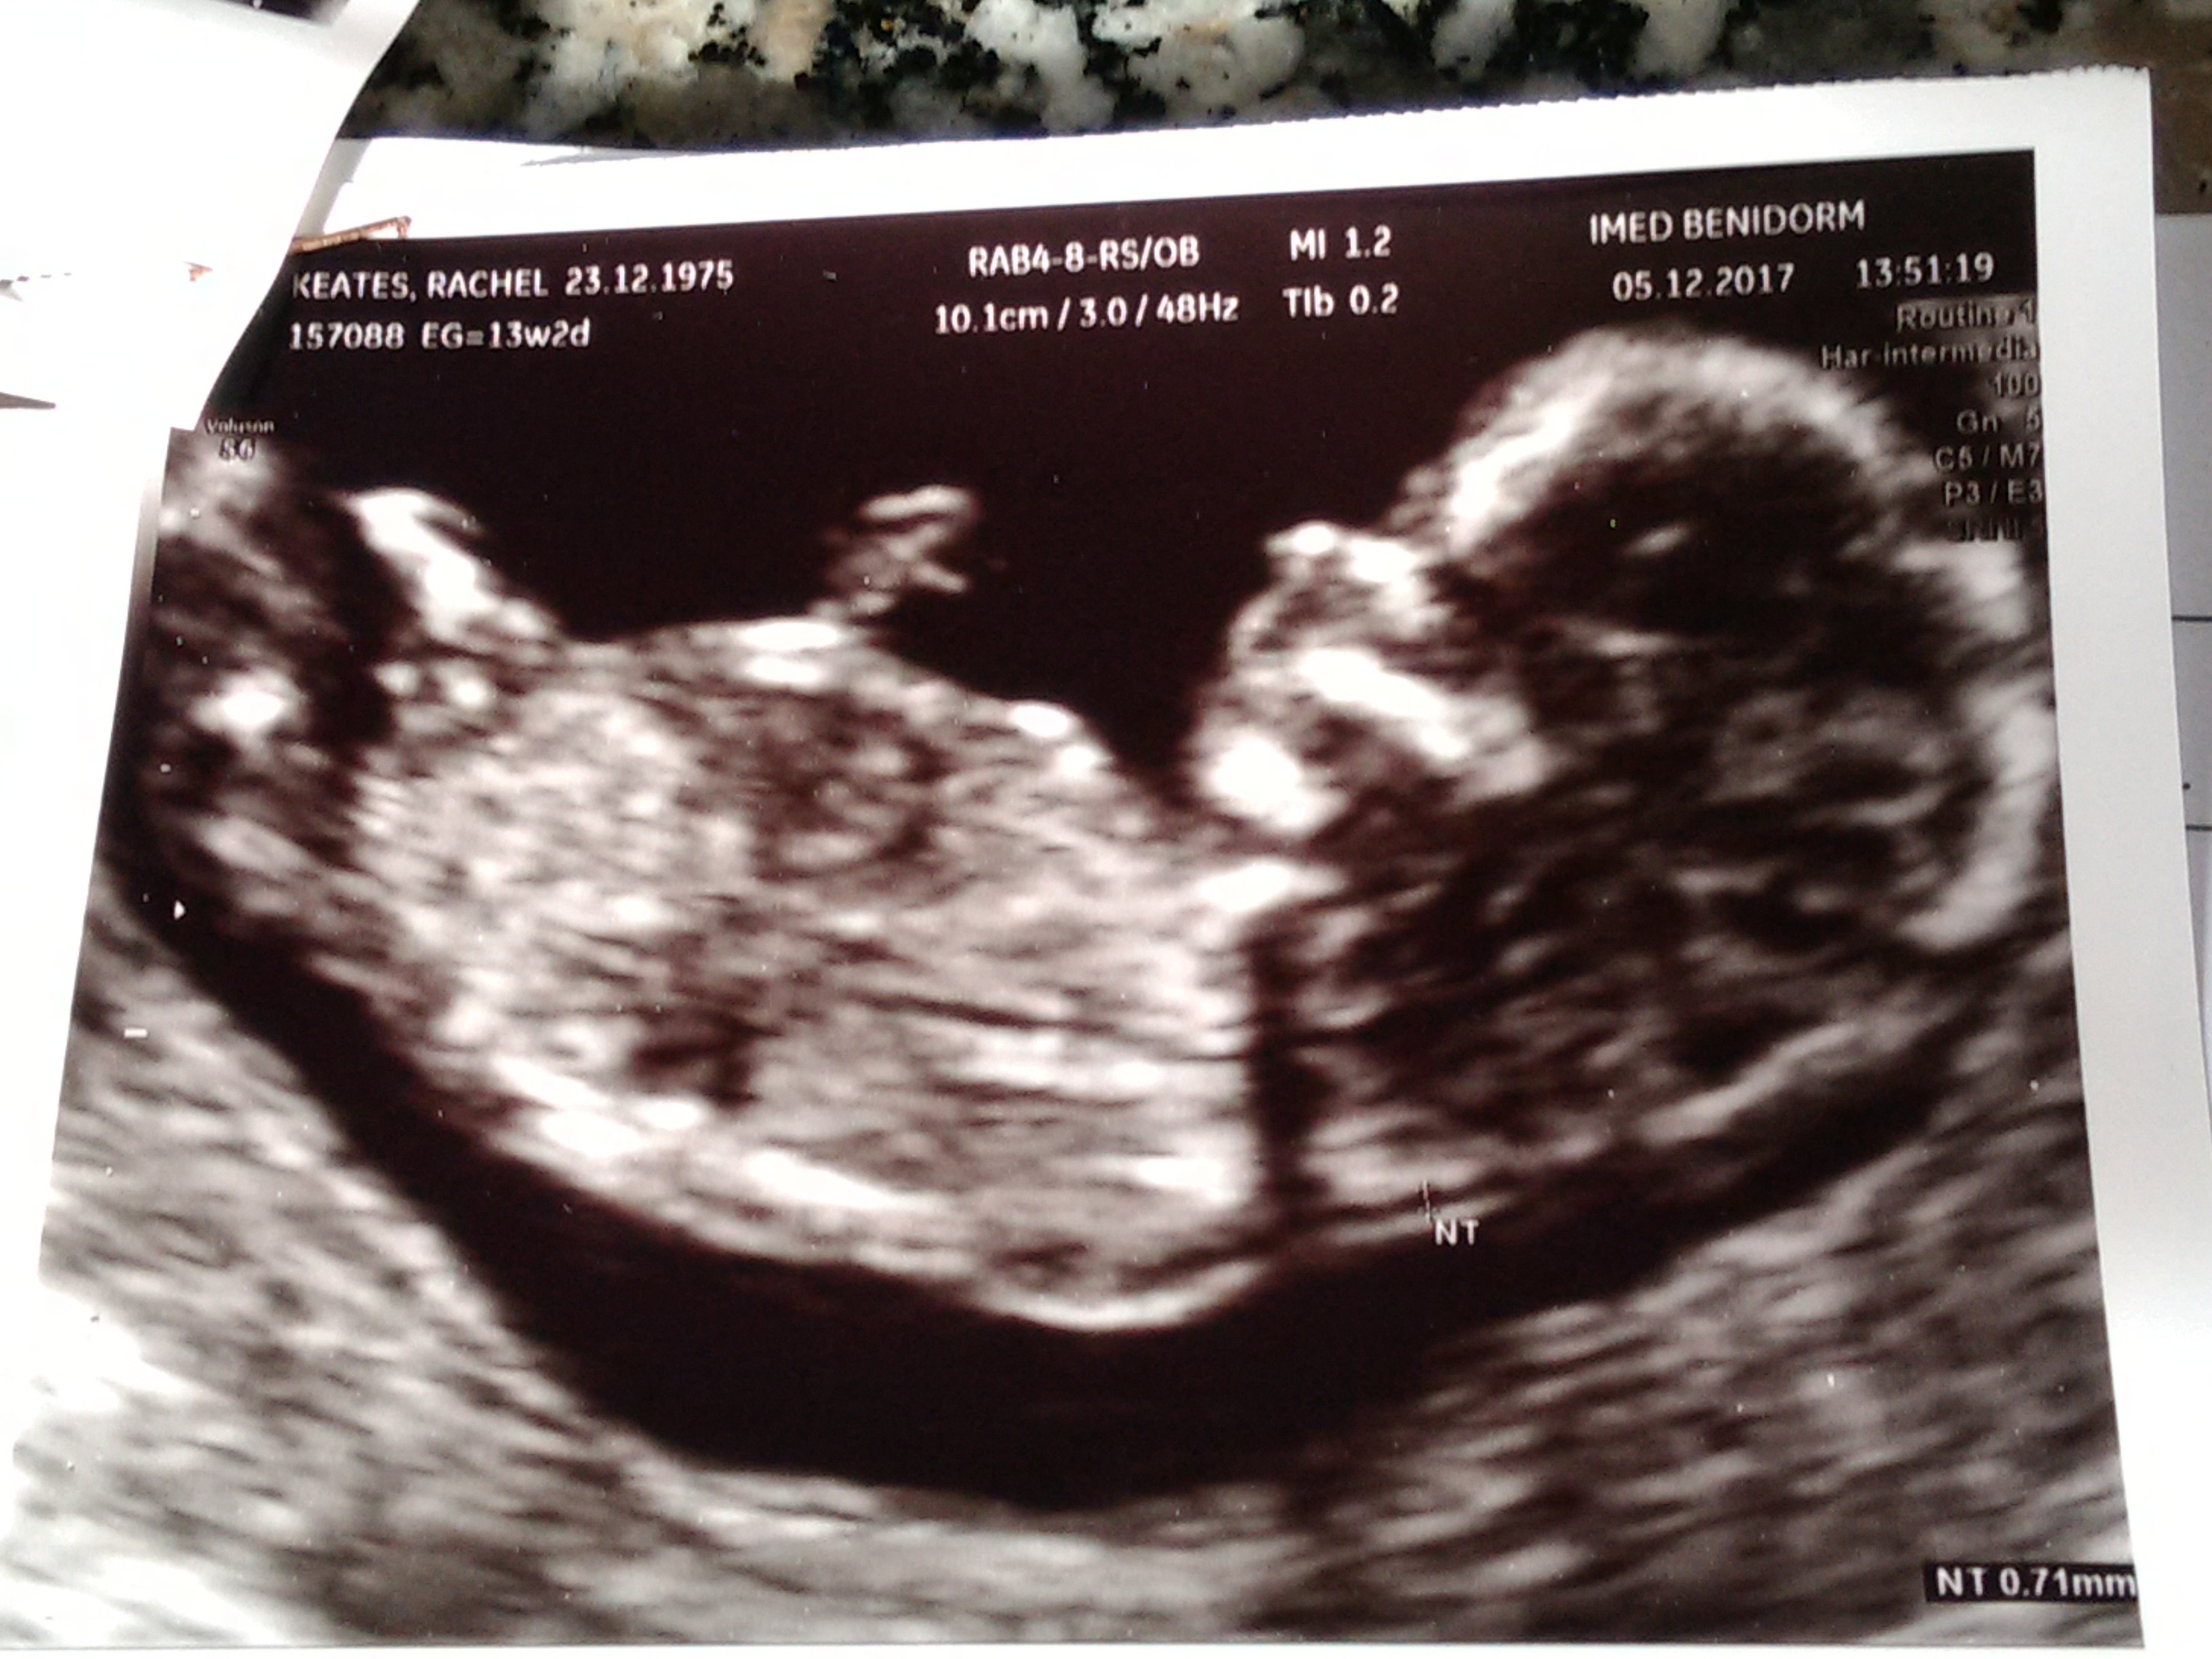

I hope you can see the pic better than when I preview my post and the image is huge... I don't know how to change it. Thanks for looking! Xx

I'm not sure I see a nub, sorry! Maybe in the first pic it might be a bit of a boy nub but I don't know if that's the nub, the pic isn't very clear.

Sorry, no clues are visible in these pics. Do you have any others?